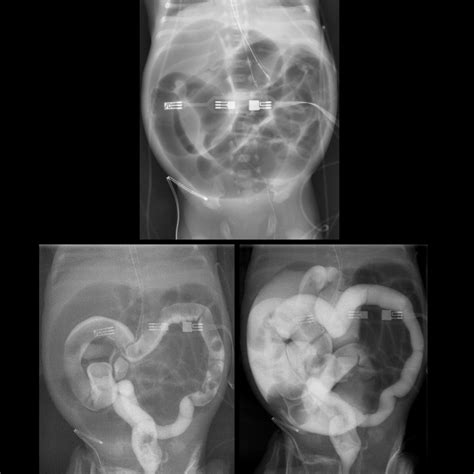

• Intussusception: This is a serious condition where one part of the intestine slides into another, causing a blockage. It requires immediate medical attention.

• Imaging Tests: In some cases, imaging tests such as X-rays or ultrasounds may be ordered to visualize the intestines and identify any blockages or abnormalities.

• Surgical Intervention: In severe cases, such as intussusception or NEC, surgical intervention may be necessary.